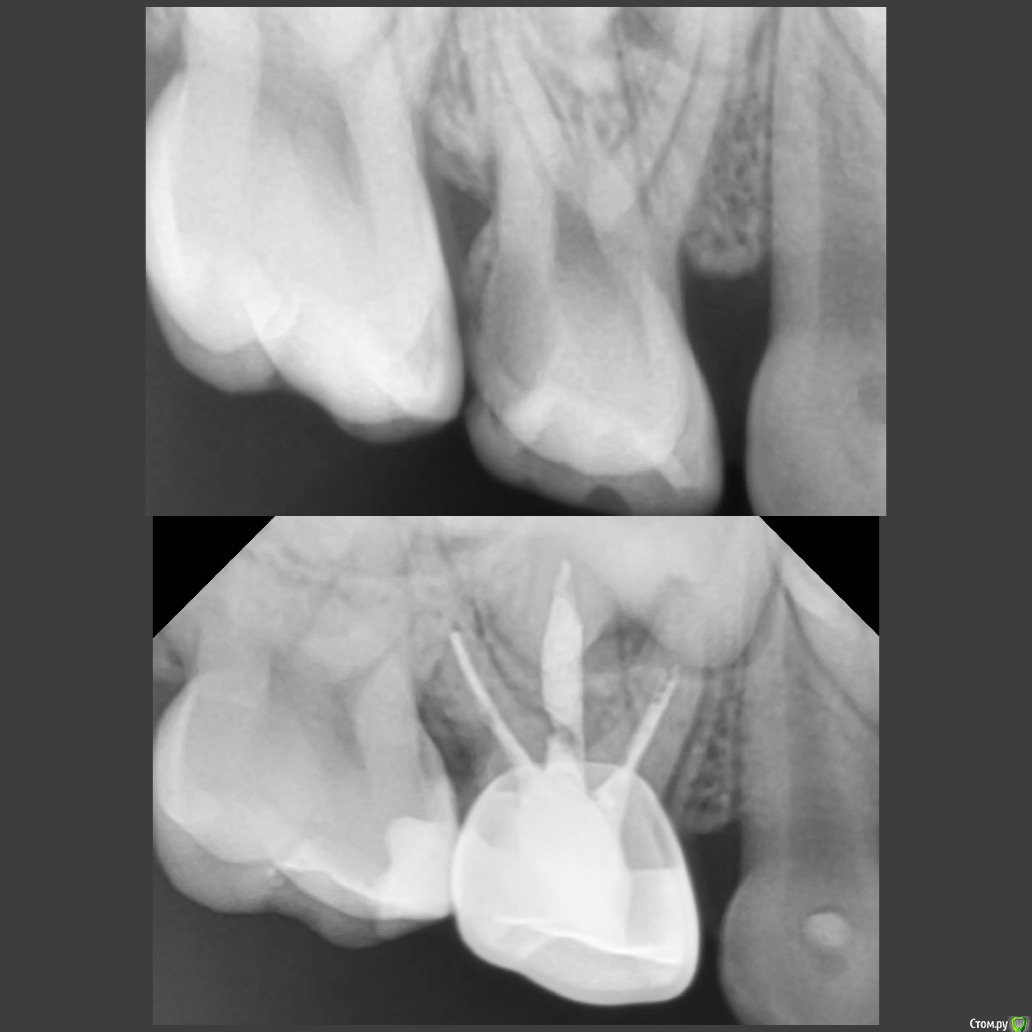

CRAZYDUCK Опубликовано 22 мая, 2018 Автор Поделиться Опубликовано 22 мая, 2018 Сначала текст , ниже фото .Даша , 5,5 лет . Лечение кариеса 5.5, кариеса 5.3 , необратимый пульпит 5.4. Продолжительность 1час 30 минут ( с момента входа в кабинет, выбора мультика и до расставания).«Скрытый» кариес медиальной контактной поверхности 5.5 подтверждён RVG. Я указала на него синими стрелочками ( листайте). 5.3 обработала рондофлекс и немного микромотором .5.4 - видно , что после ампутации гемостаза нет( полость заполнена кровью). Экстирпация машинный sx, ручные файлы 25.02; промываю гипохлорит 3%. В каналах Йодотин.культя 5.4 восстановлена IRM. Коронку фиксирую на айрекс-цем.Контрольный снимок. 1 Ссылка на комментарий

CRAZYDUCK Опубликовано 22 мая, 2018 Автор Поделиться Опубликовано 22 мая, 2018 (изменено) И про короночки ловите. 8.4 и 8.5 ранее ( около двух лет назад ) лечены методом витальной ампутации . Реставрации обширные плюс начался кариес контактных поверхностей . Два года назад я не применяла так широко в практике своей Коронки ( сейчас бы покрыла сразу после ампутации). Изменено 22 мая, 2018 пользователем CRAZYDUCK 1 Ссылка на комментарий

crown Опубликовано 22 мая, 2018 Поделиться Опубликовано 22 мая, 2018 8.4 похоже что есть изменения в бифуркации? Да надо возвращаться к коронкам. Вы где учились их ставить? Ссылка на комментарий

CRAZYDUCK Опубликовано 23 мая, 2018 Автор Поделиться Опубликовано 23 мая, 2018 В нижних 4 часто такая зона, даже в интактных. Я тоже на эту зону всегда недоверчиво смотрю. Я напишу Вам в личку позже где училась . 8.4 похоже что есть изменения в бифуркации? Да надо возвращаться к коронкам. Вы где учились их ставить? Ссылка на комментарий